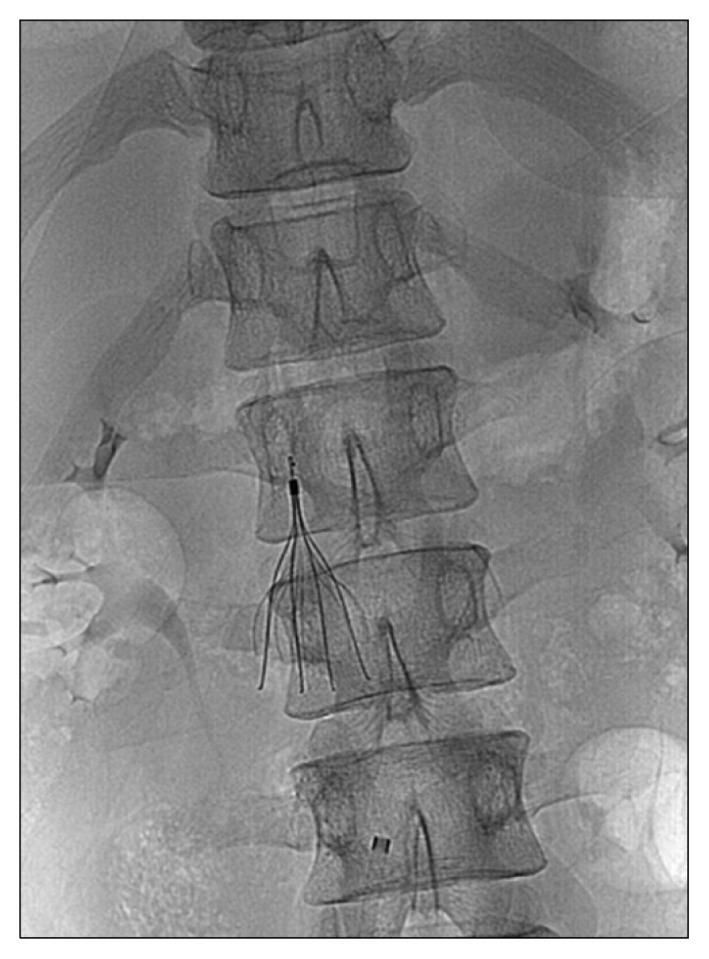

下腔静脉滤器支杆断裂后的血管外迁移

Extravascular Migration of a Fractured Inferior Vena Cava Filter Strut.

A 20-year-old man presented with a femur fracture and epidural hemorrhage (EDH) following a fall. One month after fracture surgery, swelling developed in both legs, and he was diagnosed as having a deep-vein thrombosis and pulmonary embolism. A retrievable inferior vena cava filter (IVCF) was inserted, because EDH is a contraindication to anticoagulants. Four months later, he complained of abdominal pain, and a computed tomography scan showed a fractured IVCF strut. After percutaneous removal failed 3 times, the IVCF was surgically removed by orthopedists using a portable image intensifier without cardiopulmonary bypass.

摘要

一名20岁男性在跌倒后出现股骨骨折和硬膜外血肿(EDH)。骨折手术后一个月,双腿出现肿胀,他被诊断为深静脉血栓形成和肺栓塞。由于硬膜外血肿是抗凝剂的禁忌证,因此植入了可回收下腔静脉滤器(IVCF)。四个月后,他主诉腹痛,计算机断层扫描显示IVCF支柱骨折。经皮取出失败3次后,骨科医生使用便携式影像增强器在无体外循环的情况下通过手术取出了IVCF。